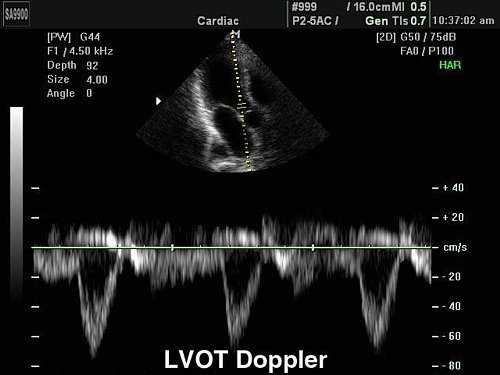

Импульсно-волновой допплер - Pulsed Wave

Импульсно-волновой допплер (Pulsed Wave или PW) применяется в эхографии для количественной оценки кровотока в сосудах. На временной развертке по вертикали отображается скорость потока в исследуемой точке. Потоки, которые двигаются к датчику отображаются выше базовой линии, обратный кровоток (от датчика) - ниже.

Максимальная скорость потока зависит от глубины сканирования, частоты импульсов и имеет ограничение (около 2,5 м/с при диагностике сердца). Высокочастотный импульсный допплер (HFPW - high frequency pulsed wave или HPRF - high pulse repeat frequency) позволяет регистрировать скорости потока большей скорости, однако тоже имеет ограничение, связанное с искажением допплеровского спектра.

В эхокардиографии, помимо формы и характера кровотока, с помощью импульсного допплера можно зафиксировать щелчки открытия и закрытия створок клапанов, дополнительные сигналы от хорд створок и стенок сердца.